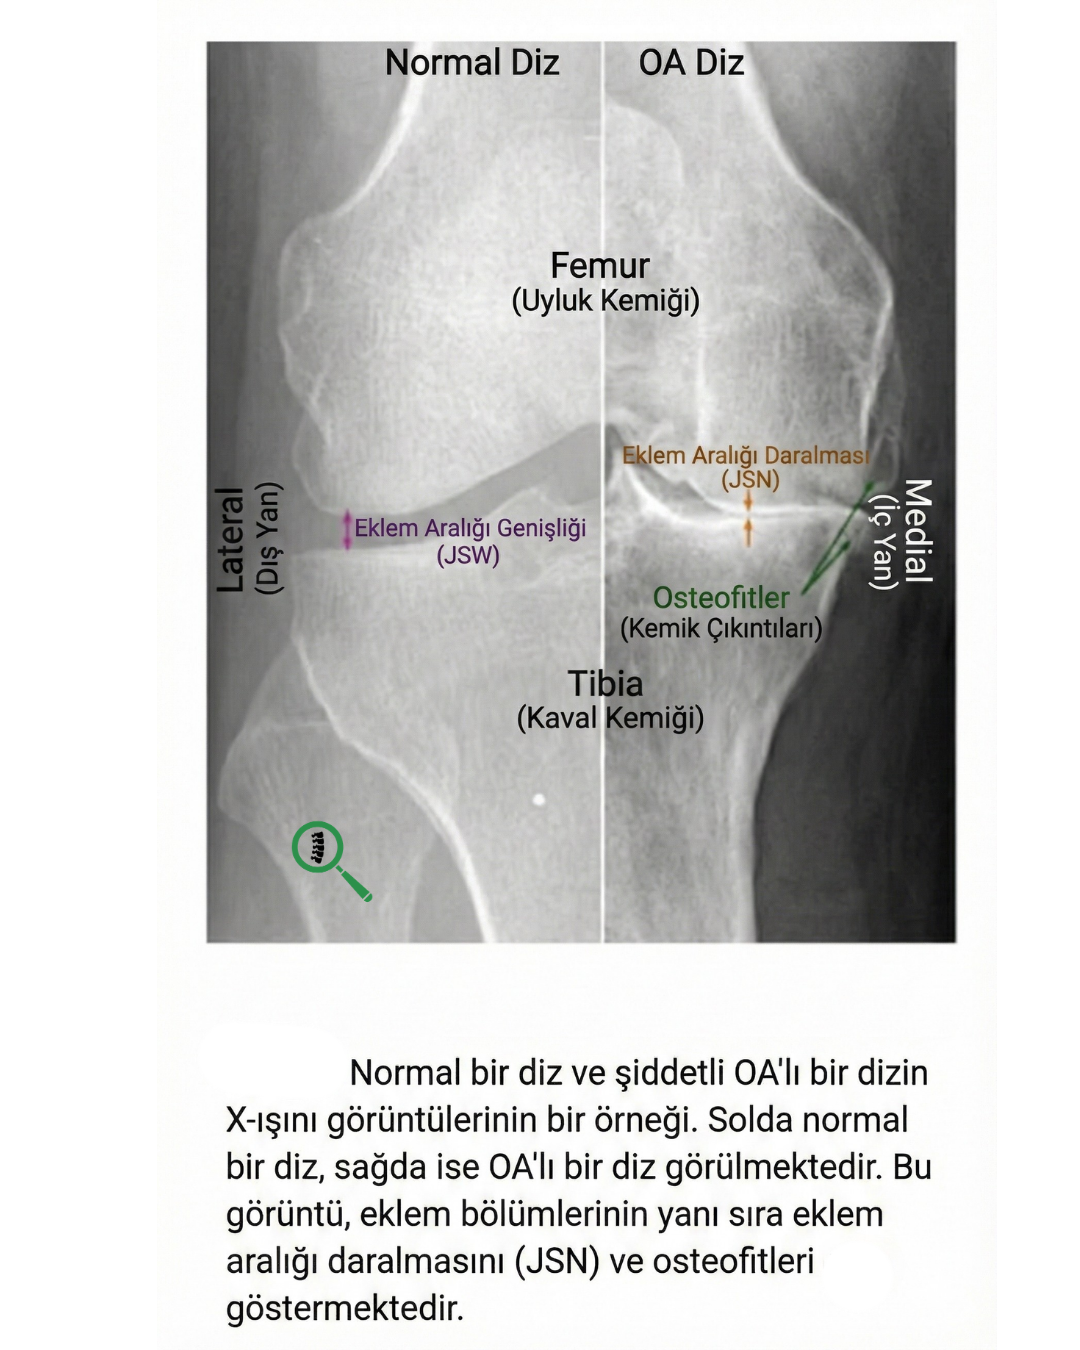

- Röntgen (X-Ray): Kireçlenme tanısında kullanılan ilk ve en temel görüntüleme yöntemidir. Röntgende kıkırdak dokusu doğrudan görünmese de, kıkırdak aşındıkça kemikler arasındaki boşluğun daralması ve eklem kenarlarında "osteofit" adı verilen yeni kemik çıkıntılarının oluşmasıyla kireçlenme anlaşılır.

Bu durum dizde ağrı, şişlik ve özellikle sabah uyandığınızda veya uzun süre hareketsiz kaldığınızda fark edilen bir sertliğe yol açar. Kireçlenme ilerledikçe eklem çevresinde "kemik çıkıntıları" (osteofit) oluşabilir ve dizin hareket açıklığı kısıtlanabilir. Genellikle orta yaş ve üzerindeki bireylerde görülen bu rahatsızlık; kıkırdak, kemik ve eklem sıvısını kapsayan kronik bir süreçtir.

- Şekil Bozukluğu ve Sert Yumrular: İleri evrelerde dizin normal yapısı bozulabilir. Ayrıca eklem kenarlarında "osteofit" denilen ve ele sert yumrular gibi gelen yeni kemik oluşumları fark edilebilir.